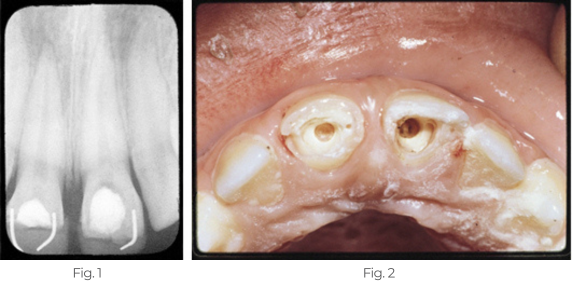

Bildung einer Dentinbrücke

Fall 2

Der Patient stellte sich unter Schmerzen mit gebrochenen oberen zentralen Schneidezähnen und freiliegender Pulpa vor. Es wurden Pulpotomien mit Pulpdent Paste als Pulpaverband durchgeführt, der mit Zinkphosphatzement versiegelt wurde. Es wurden Kompositrestaurationen mit Stiften zur Retention eingesetzt. Ein Jahr nach den Pulpotomien kam der Patient für weitere ästhetische Kompositrestaurationen zurück.

Eine Röntgenaufnahme nach einem Jahr zeigt zwei neue Brücken aus dichtem Dentin mit Komposit, die mit Stiften befestigt sind.

Abb. 1; Dies ist eine seltene Aufnahme der neuen Dentinbrücken nach Entfernung des Komposits, der Stifte und des Zinkphosphatzements.

Abb. 2: Multi-Cal kann auch für die Bildung von Dentinbrücken bei direkter Pulpaüberkappung, Pulpakürettage und vitalen Calciumhydroxid-Pulpotomien verwendet werden.